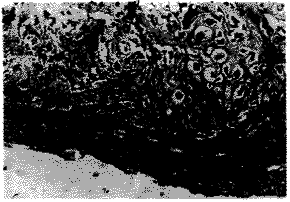

2.组织学观察:A组4天时,骨外膜下可见间充质细胞和成纤维细胞大量增生,局部组织隆起形成丘状结构,但骨外膜无明显变化,7天可见增生组织中出现大量形态幼稚的软骨细胞,细胞扁圆、体积较小,也有少数成熟的软骨细胞,体积大、圆形,形成软骨巢(图1),同时在软骨巢周围可见膜内成骨现象,新生的类骨质在骨膜下沿骨干方向排列,着色浅红。14天软骨巢增大,并向下侵蚀骨干的皮质骨,软骨细胞趋向成熟,细胞圆形、核大,胞浆呈嗜碱性,周围的膜内成骨区域骨小梁形成,着色加深(图2),21天出现软骨内骨化,软骨细胞变性、死亡,出现大量成骨细胞,分泌骨基质,形成原始骨小梁,周围膜内成骨的骨小梁成熟,着色深,形成骨髓腔,腔内可见破骨细胞及红细胞(图3)。

图1 A组7天时,增生组织中出现大量幼稚软骨细胞及

少数较成熟的软骨细胞,形成软骨巢 HE×400